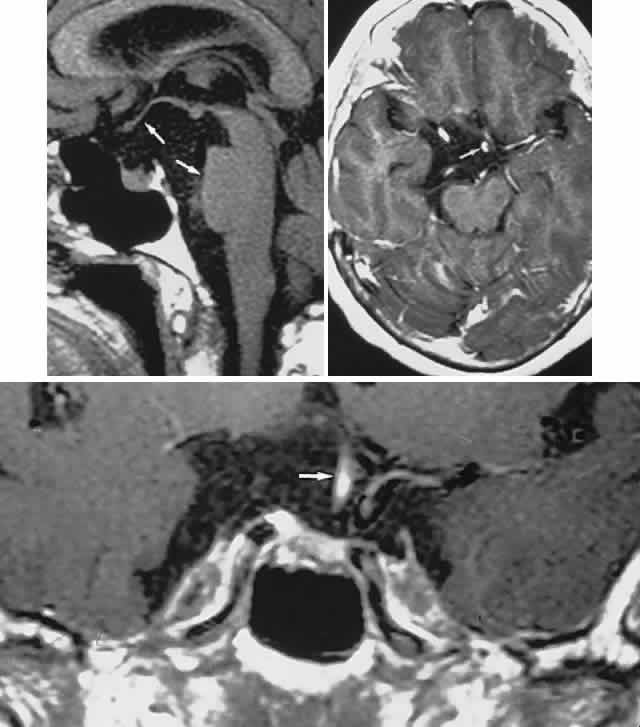

Fig. 2. Large prolactinoma. Original vision in the right eye (RE) was 8/200, left eye (LE) 1/200, with serum prolactin of 26,000 ng/ml and galactorrhea. Four months of bromocriptine reduced prolactin to 661 ng/ml, vision improved to RE 20/40, LE 20/50. At 3 years, vision was as follows: RE 20/30, LE 20/20; prolactin was 25.9 ng/ml. Enhanced magnetic resonance imaging. Sagittal (A) and coronal (C) images at diagnosis. Sagittal (B) and coronal (D) images at 2-year follow-up, showing dramatic shrinkage of the mass.

With the advent of the ergot-derived dopamine agonist bromocriptine, there is a pharmacologic alternative (or adjunct) to surgery for prolactinomas. Bromocriptine (2-bromo-alpha-ergocryptine) is representative of a class of ergot derivatives that, since the early 1970s, have been known to inhibit pituitary gonadotropic function, reduce PRL secretion, and diminish the size of pituitary tumors (see Fig. 2). Such ergot derivatives are structurally related to dopamine, a PRL-inhibitory factor elaborated by hypothalamic dopaminergic neurons. It is likely that bromocriptine acts in two ways: dopamine turnover in tubero-infundibular neurons is depressed, thereby increasing hypothalamic dopamine; dopamine receptors of the pituitary are inhibited, reducing both spontaneous PRL secretion and the release of PRL provoked by thyrotropin-releasing hormone. At any rate, bromocriptine decreases PRL production and secretion, with resultant reduction in lactotrope size and subsequent diminution of tumor volume, often rapidly, within 1 to 2 hours of initiation of treatment.25